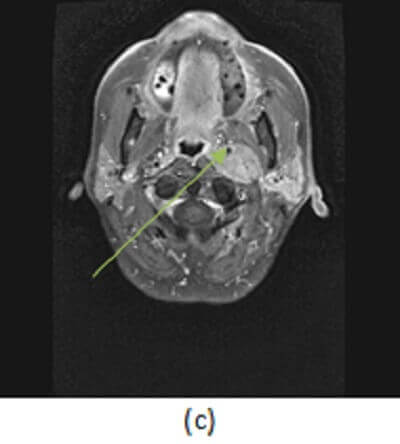

Figure 1: (a,red arrow) contrast enhanced neck CT demonstrates a homogenously enhancing carotid space mass that displaces the right ICA anteromedially. MR soft tissue neck from a different patient with the same diagnosis show a T2 hyperintense (b, blue arrow) mass that homogenously enhances with the exception of a few low attenuation foci within the mass (c,green arrow) suggestive of small flow voids. These findings are consistent with a paraganglioma of the glomus vagale.

Paraganglioms are avidly enhancing tumors that have a characteristic salt and pepper appearance on MRI due to the presence of vascular flow voids interspersed within enhancing tumor parenchyma.